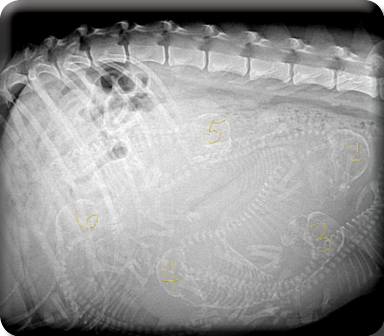

Only a few hours old Empress Maya and Damien Czar's puppies snuggle up in Empress Maya's fluffy tail.

There's Todd aka Hot Rod Todd, Haku aka BBQ Haku, Echo aka Eye Patch Echo. Simba aka HRH Simba, Koda aka Morse Koda and last but not least the superstar to be, Merc aka Rock Star Merc.

Below, BBQ Haku gives mum Empress Maya puppy kisses